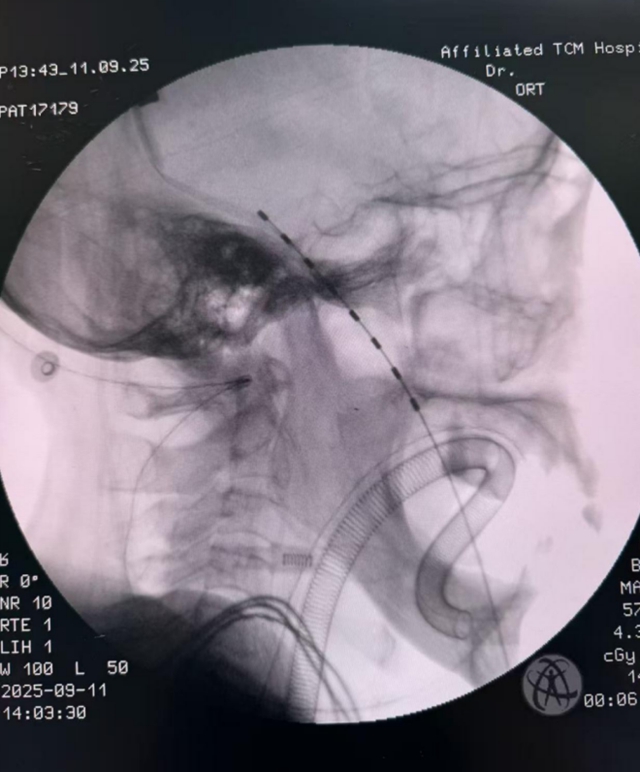

考虑到老人家对疼痛和手术的承受力有限,张英教授带领韩聪、徐力医生团队,创新采用了“全麻下C臂引导经皮穿刺左侧卵圆孔脊髓电刺激系统植入术”。

这个听起来复杂的名字,核心就是:在精密的影像设备引导下,通过皮肤上的一个小穿刺点,将一根精细的电极精准送到患病的神经附近。